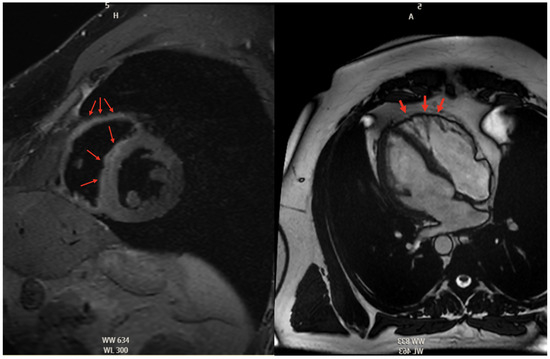

5.2.3. Cardiac Magnetic Resonance High Risk